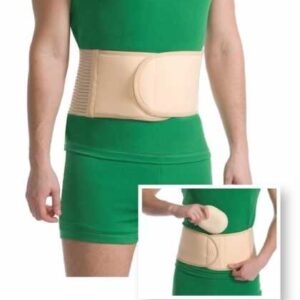

MEDTEX 5051 CORSET HERNIE OMBILICALA MARIME XS/S 50-70CM